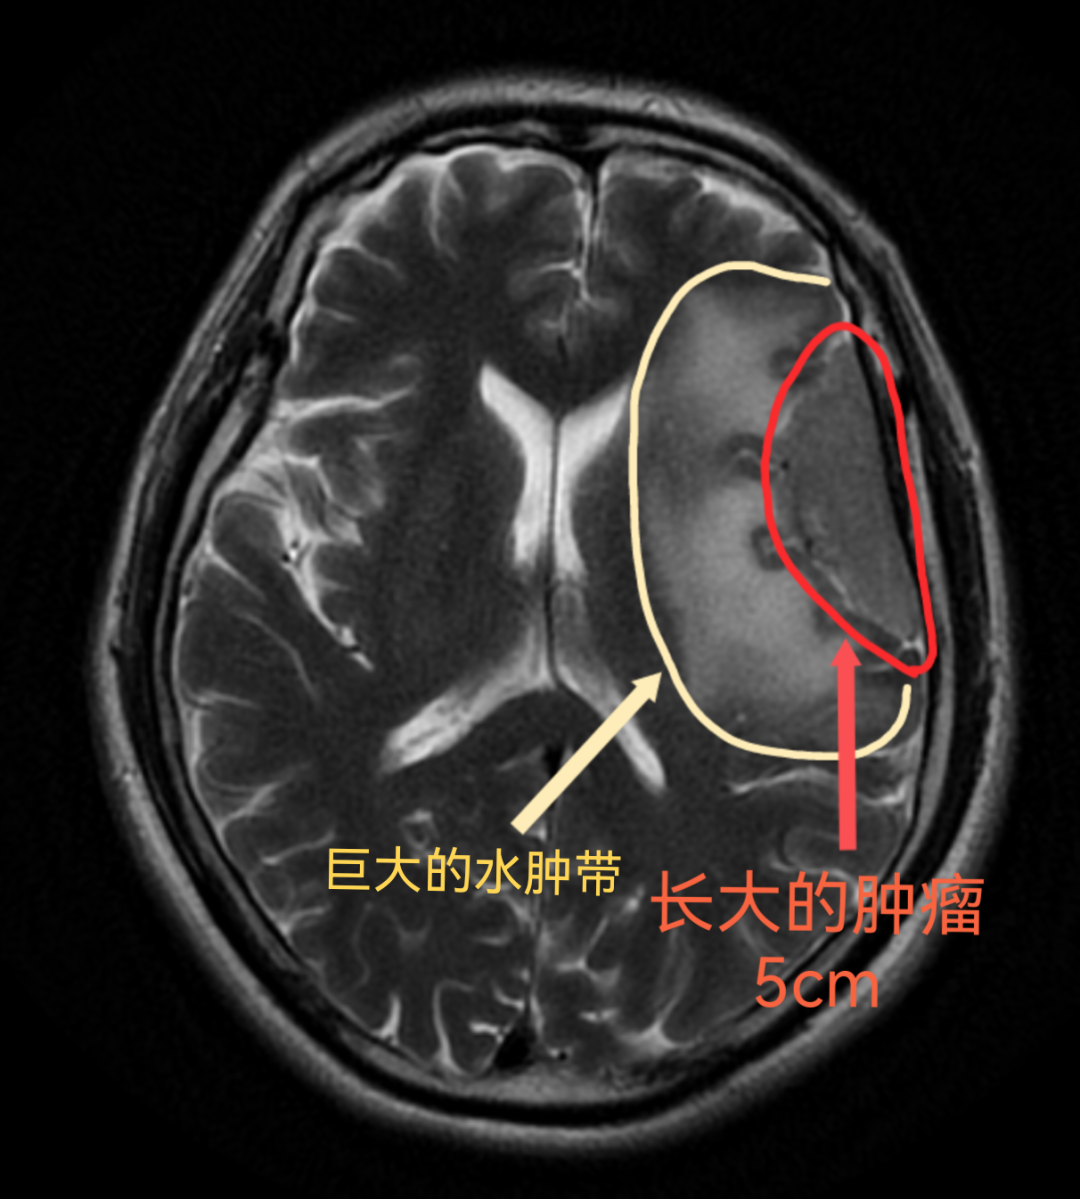

近日,我院神经外科团队成功为一名巨大脑肿瘤患者实施高难度切除手术。60岁患者朱先生(化名)五年前体检发现左侧额叶1cm脑膜瘤,因无头痛、呕吐等症状选择观察,后续未出现明显症状,也就未再复查该肿瘤。近期患者突发癫痫,出现肢体抽搐、失语、一过性意识丧失的症状,紧急送往我院神经外科就诊。经检查,肿瘤已增长至5cm并压迫运动功能区和语言区,直接趴在侧裂血管、大脑中动脉上。

手术风险不仅在于巨大肿瘤十分靠近功能区,还包括患者存在的高血脂、高血压、颈动脉狭窄等多种基础疾病。在医务科组织下,神经外科蔡璞主任团队联合影像科、麻醉科、心内科、呼吸内科、神经内科、重症监护室、营养科等多科开展MDT会诊,最终确定手术方案:3D重建技术精准定位肿瘤与运动区关系,显微镜下实现毫米级切除。

脑肿瘤有良恶性的区别,其中脑膜瘤虽多属良性,但持续生长会像膨胀的气球一样危及脑组织,肿瘤小时切除风险较小,随着肿瘤的增大手术风险会呈指数难度上升,所以需要早发现、早诊断、早治疗。